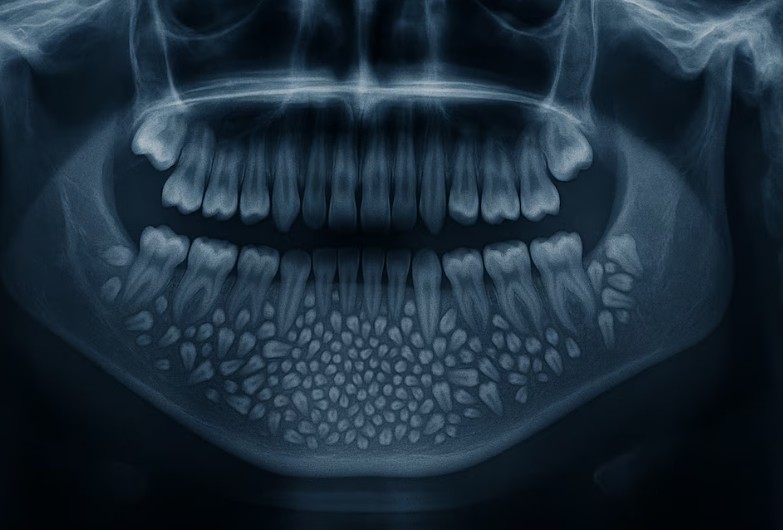

Las radiografías y tomografías computerizadas revelaron la presencia de una masa de aproximadamente 200 gramos alojada en el interior de la mandíbula. El Dr. Senthilnathan, responsable del Departamento de Cirugía Oral y Maxilofacial, identificó la anomalía como un “odontoma compuesto”, una variante benigna de tumor directamente relacionada con el desarrollo dental.

“La especie de tumor que detectamos impidió el crecimiento permanente de los molares en el niño en el lado afectado”, explicó el cirujano tras completar la operación. Las imágenes médicas mostraban numerosos dientes rudimentarios agrupados en un tejido con forma de bolsa, una presentación clínica poco frecuente en la literatura especializada.

La magnitud del descubrimiento sorprendió incluso a los médicos más experimentados. Según informó Science Alert, la bolsa contenía 526 pequeños dientes de dimensiones variables, desde apenas 0,1 milímetros hasta 15 milímetros de longitud. El proceso de clasificación y contabilización de cada pieza dental requirió cinco horas adicionales de trabajo meticuloso en el laboratorio.

La Dra. Pratibha Ramani, directora del Departamento de Patología Oral y Maxilofacial, destacó que todos los dientes extraídos presentaban las estructuras características de las piezas dentales normales: corona, raíz y recubrimiento de esmalte. “Incluso la pieza más pequeña tenía las características de un diente tradicional”, subrayó la especialista, quien enfatizó la ausencia de precedentes con tal número de dientes en los registros médicos mundiales.